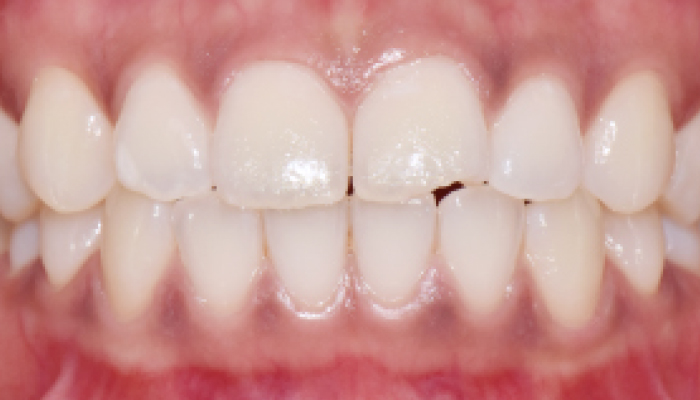

이갈이는 다양한 원인에 의해 발생되는 것으로 치아의 마모, 턱관절 통증, 두통 등을 유발합니다. 치과치료와 함께 생활습관을 교정하는 방법으로 이갈이를 줄여나갈 수 있습니다.

다양한 합병증을 동반하는 이갈이